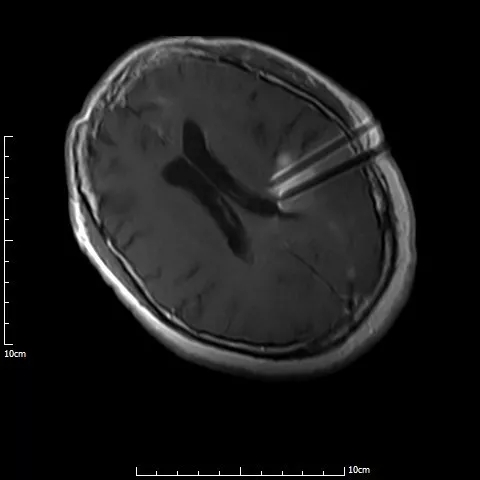

介入手术治疗中,

磁共振实时引导技术保证介入手术过程在可视化下连续性完成

手术过程仅半小时,先对满女士进行局麻,然后在1.0T开放式介入磁共振监控及3D打印模板引导下,

李成利主任将4根磁共振兼容性穿刺针平行穿刺至肿瘤病变既定位置,根据近距离放疗计划植入I125放射性粒子,

该粒子通过持续释放低剂量γ射线对肿瘤细胞起到杀伤作用,而且对周边正常脑组织损伤较小。

术中磁共振显示,4根穿刺针平行准确穿刺至病灶内